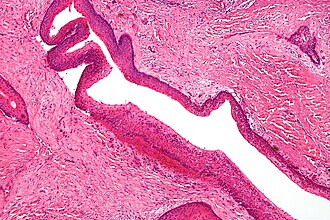

Keratocystic odontogenic tumour. H&E stain. | |

| LM | stratified epithelium with "ribbon-like appearance" with palisaded basal cell layer, parakeratosis, artefactual separation of epithelium from the basement membrane |

- Stratified epithelium (resembling squamous epithelium) with:

- "Ribbon-like appearance" - important.

- Typically 8-10 cell layers thick - with relatively uniform thickness.

- Lacks rete ridges.

- Palisaded basal cell layer.

- Parakeratosis (keratinized cells with nuclei) - key feature.

- Artefactual separation of epithelium from the basement membrane.

Right Maxillary Sinus Mass, Excision:

- Consistent with odontogenic keratocyst (benign ribbon-like squamous epithelium

with keratinization, separated from the underlying hyaline stroma with cartilage).